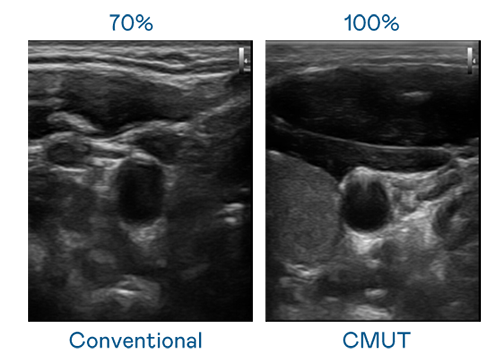

CMUT 技术是一种用电容式微机电元件来产生超音波讯号的技术。与传统 PZT 压电式技术相比,CMUT 频宽增加 30%,更宽频的超音波讯号让影像解析度大幅提升,是实现高影像品质医疗超音波扫描、促进精准医疗发展的关键技术。

超音波影像的解析度高低,首先取决于探头能发出的讯号频宽。AG旗舰厅 (中国大陆) CMUT 可提供高清晰的超音波讯号,提供高频宽、高灵敏度、影像纹理细节更高的超音波影像,协助医护人员缩短影像判读时间及利用精准的医疗影像进行诊断。